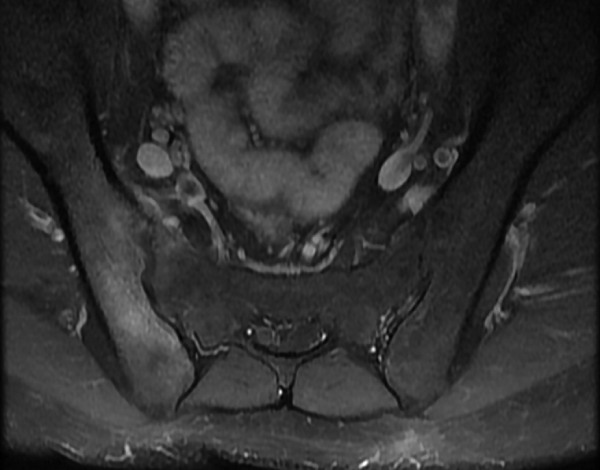

Chụp CT cho thấy hình ảnh bất thường, các mức độ tổn thương khác nhau của khớp cùng chậu. Phương pháp này cũng có thể cho thấy tình trạng khe khớp cùng chậu rộng, xơ cứng trên bề mặt khớp, bào mòn khớp, dính một phần hoặc hoàn toàn khớp cùng chậu,… Dựa vào kết quả, bác sĩ sẽ chẩn đoán tình trạng viêm của khớp cùng chậu ở giai đoạn trung bình hoặc nghiêm trọng.